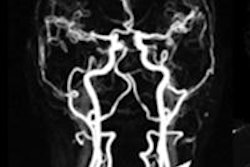

Contrast-enhanced whole-body MRI studies were performed on a 1.5-tesla scanner with conventional T1- and T2-weighted as well as diffusion-weighted sequences. Low-dose CT was also performed for the lung.

Four readers prospectively classified findings as benign or suspicious metastases and divided them into nine body regions: brain, neck, thorax, upper abdomen, liver, pelvis, soft tissues, bone, and lymph nodes. For the purposes of the study, the reference standard was biopsy or follow-up.

There were 140 findings in all body regions. Whole-body MRI produced a sensitivity of 93%, specificity of 89%, positive predictive value of 52%, negative predictive value of 99%, and diagnostic accuracy of 90%.